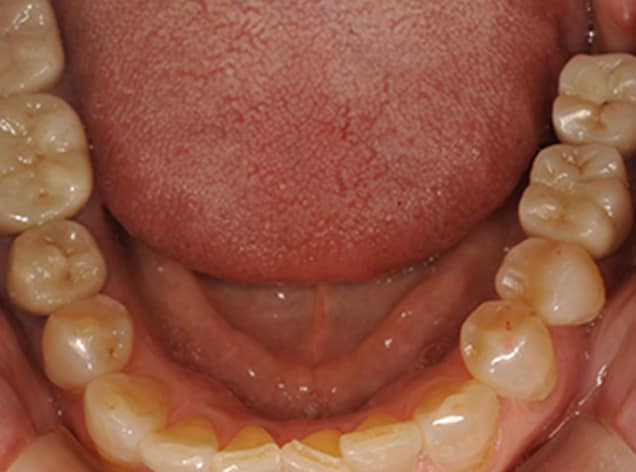

欠損部分をインプラントで治療し、下顎の歯をセラミックで審美的に改善したケース。